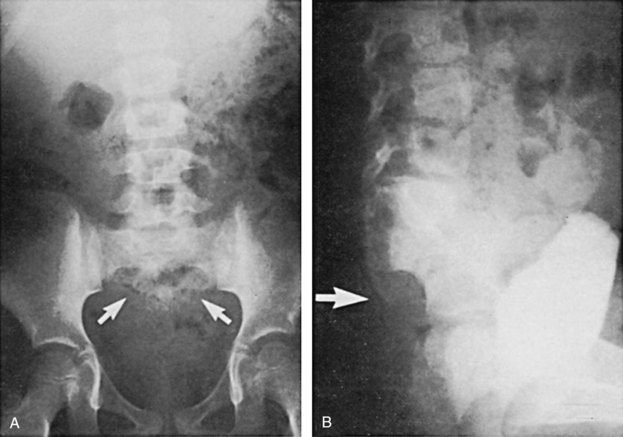

Figure 128–5 A, A voiding cystourethrogram in a female neonate with dyssynergy and elevated voiding pressures demonstrates no reflux and a smooth-walled bladder. Her initial renal echogram was normal. She was started on clean intermittent catheterization and oxybutynin chloride (Ditropan) but did not respond. Within 1 year she developed right hydronephrosis (B, arrows) and severe reflux, evident on a radionuclide cystogram (C).